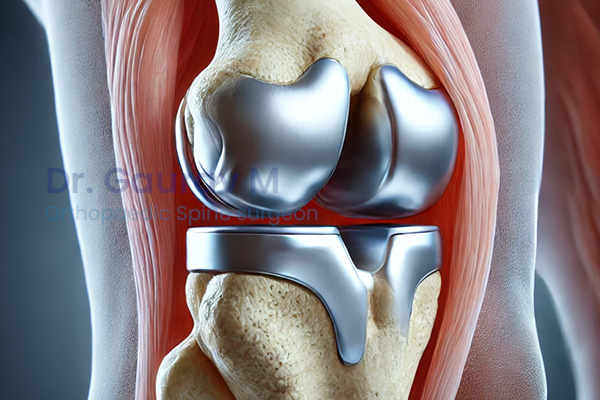

Advanced surgical solutions for damaged joints using modern implants, restoring mobility, reducing pain, and improving long-term joint function.